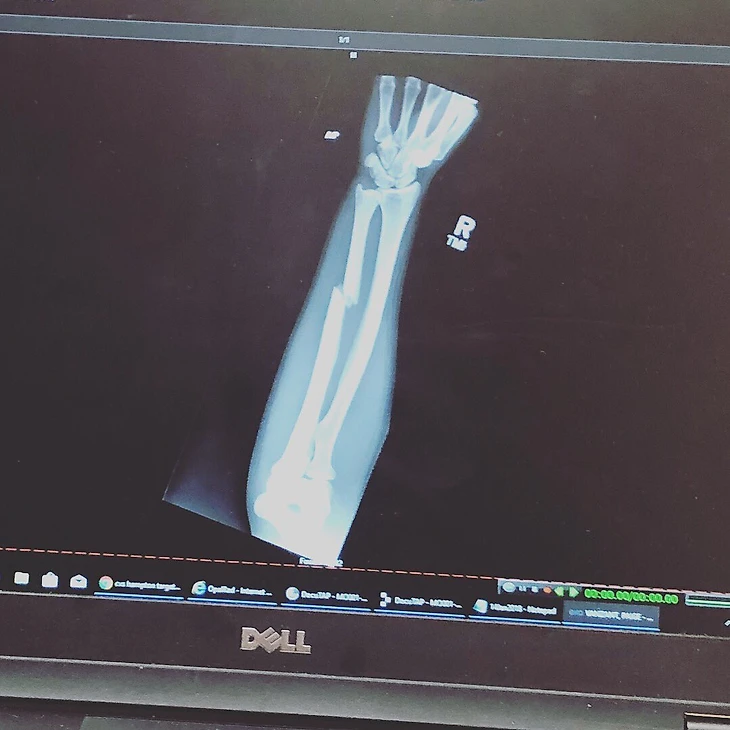

Боец наилегчаейшего веса UFC Пейдж Ванзант сломала руку во втором раунде боя против Джессики-Роуз Кларк. Девушка проиграла поединок единогласным решением судей.«В первом раунде (Пейдж ошиблась – Sports.ru) я сломала руку. Я могла драться до конца, но, как вы видели, мне было тяжело работать правой [рукой]. Спасибо UFC, моей сопернице и тренерам. Я вернусь лучше и сильнее, чем когда-либо! Это часть игры. У бога были другие планы на меня.Проклятый бэкфист», – написала Пейдж в инстаграме и выложила фото рентген-снимка.

Перелом случился во время удара «бэкфист» – Ванзант попала предплечьем сопернице в лоб.Над ней смеялись, когда она занималась танцами. Теперь она звезда UFC